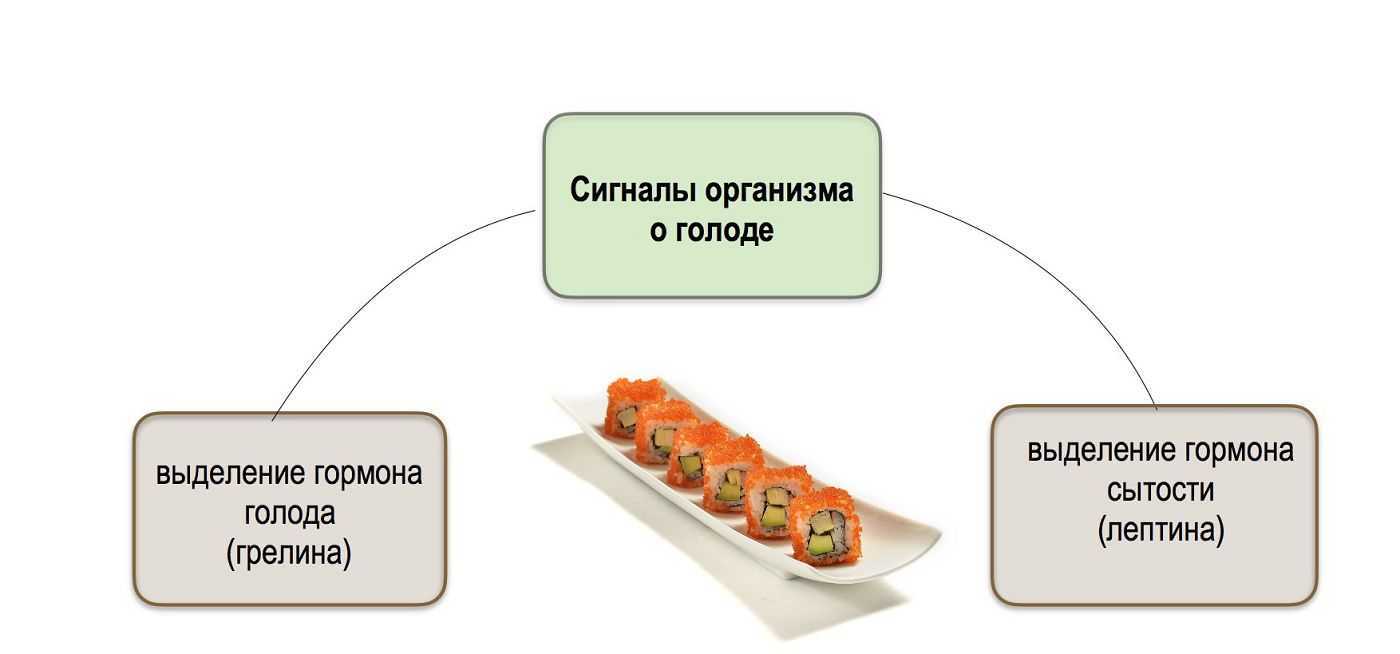

Как работает центр насыщения в гипоталамусе: визуальные иллюстрации